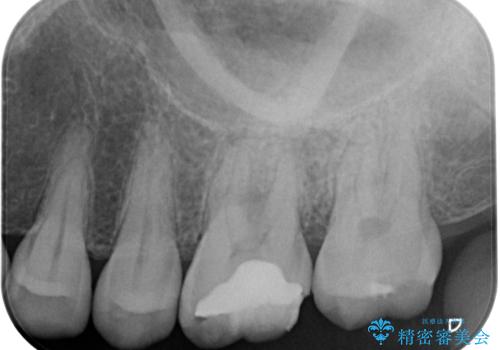

- 奥歯で咬んだときに痛みがあり、膿の出口が現れたとのことで来院された患者様です。

診査を行った結果、まずは根管治療を行うこととしました。

咬み合わせが非常に強く、臼歯のみに咬合力が集中している咬み合わせだったので、根管治療後はPGAクラウン(白金加金合金クラウン)にて補綴する治療計画となりました。